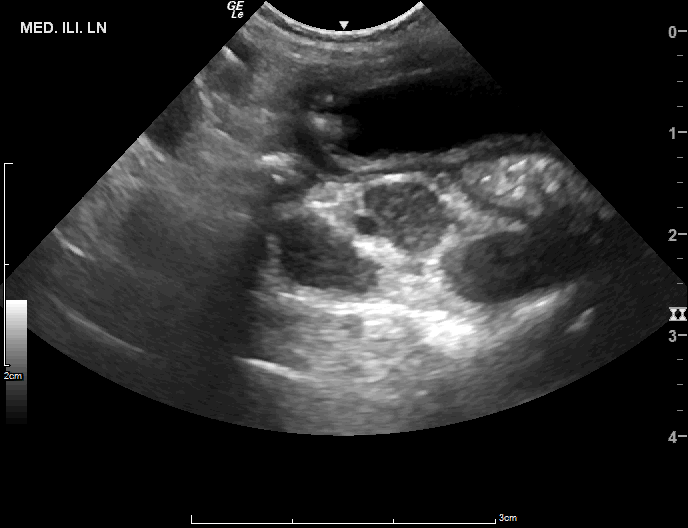

腹腔超音波檢測,腸骨下淋巴結腫大

療程期間以癌識優®檢測,觀察發現治療前所測得的癌症訊號持續下降,伴隨全身淋巴結消腫,回復正常大小。治療結束後追蹤時,先前腫大的淋巴結仍維持消退狀態,達到完全緩解。